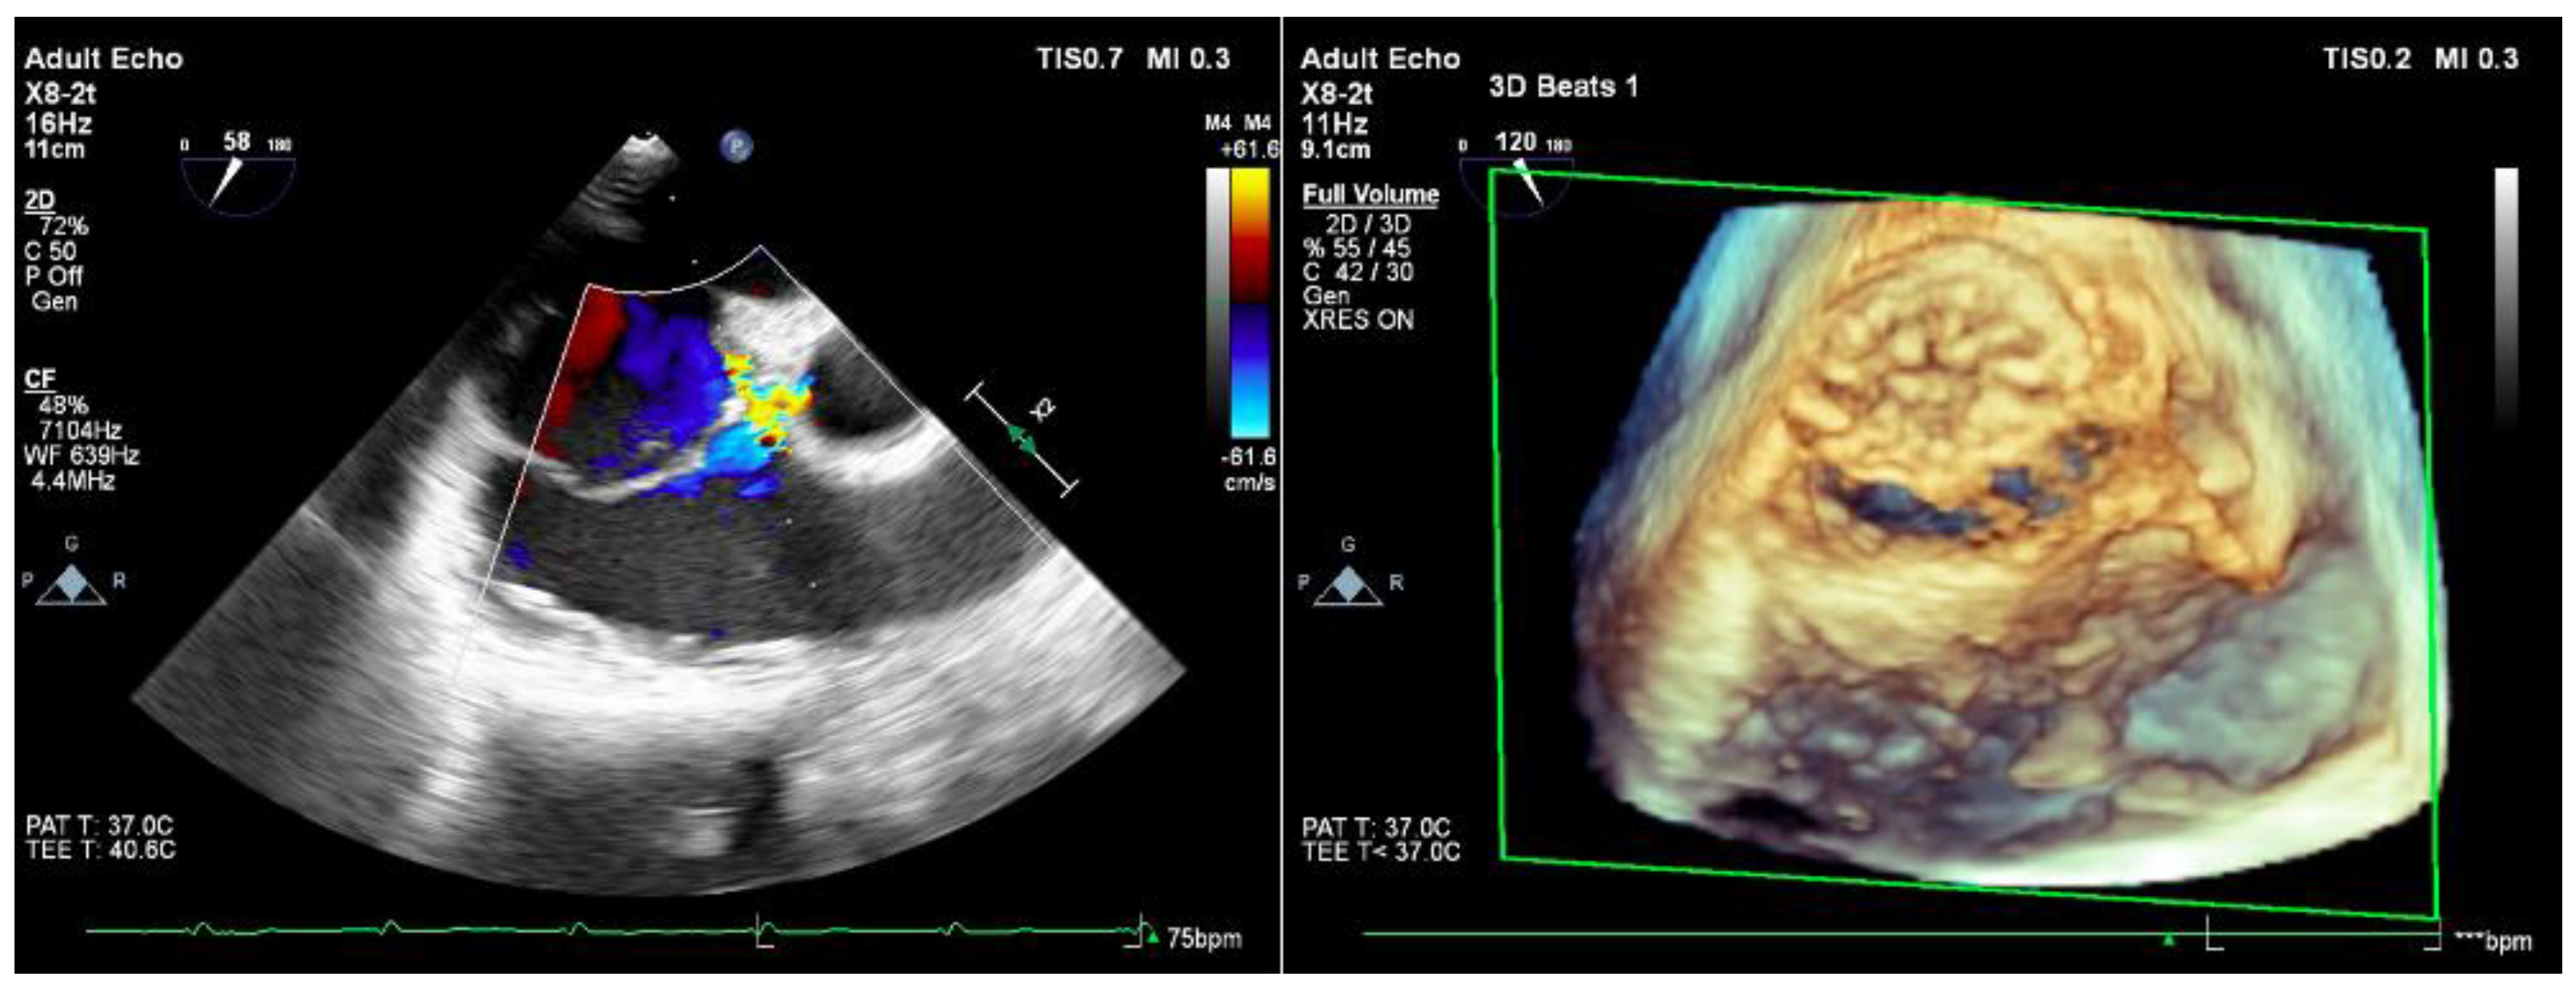

2. Case Report